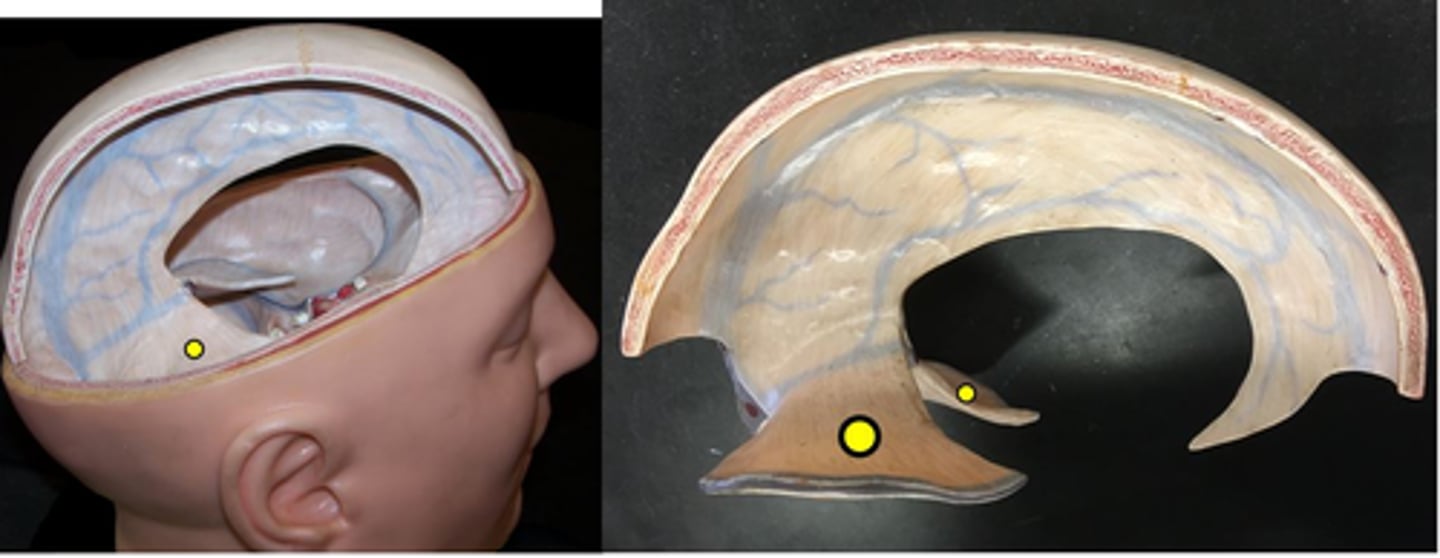

Dura mater

Number 3 on picture

Arachnoid mater

Number 2 on picture

Pia mater

Number 1 on picture

Falx cerebri

separates the two cerebral hemispheres

Tentorium cerebelli

separates cerebrum from cerebellum

Falx cerebelli

separates the two hemispheres of the cerebellum

Superior sagittal sinus

Inferior sagittal sinus

Transverse sinus